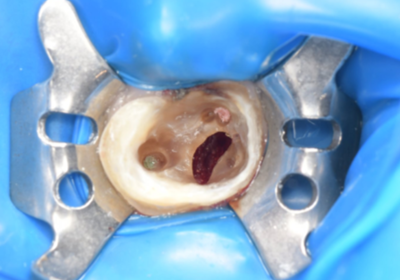

初診時デンタルX線写真とCT画像。

根管外に不透過像とそれを取り囲む透過像を認める。

コアを除去すると、分岐部へつながるパーフォレーションを認めた。

これが排膿の原因であったため、保存は困難と判断した。